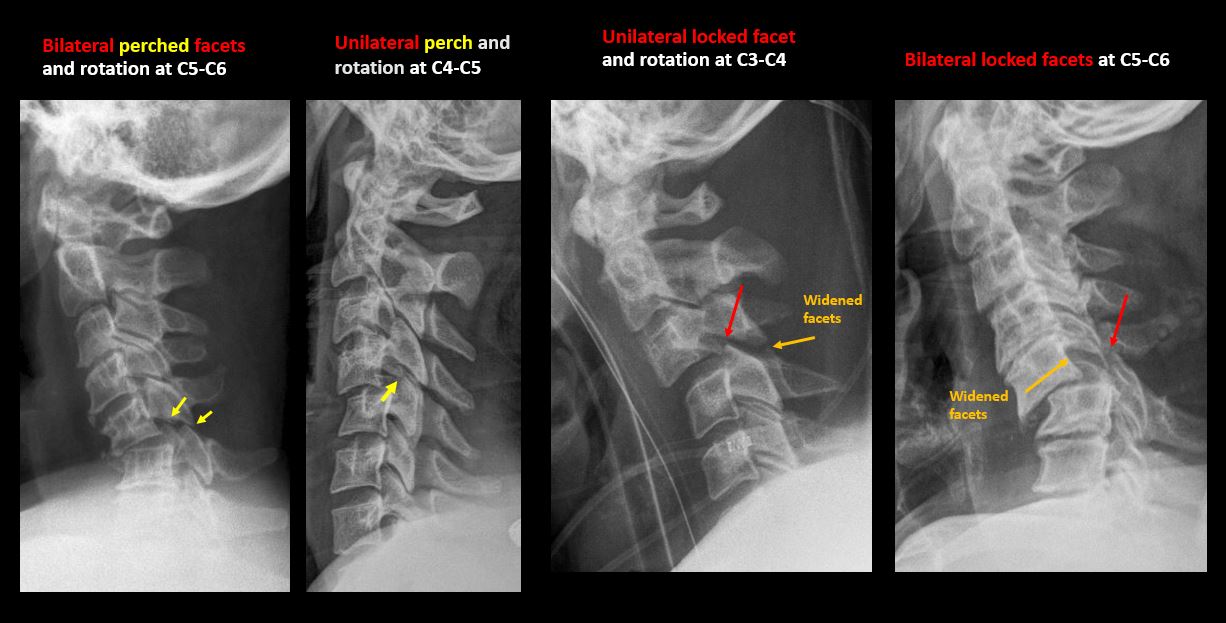

Limited flexion and extension views show evidence of ligamentous injury at C5-C6 with kyphotic deformity, bilateral perched facets, and rotational deformity. Mild anterior wedging of C5 is likely chronic.

Direct communication with the clinical team at the time of dictation regarding ligamentous injury and perched facets at C5-C6.